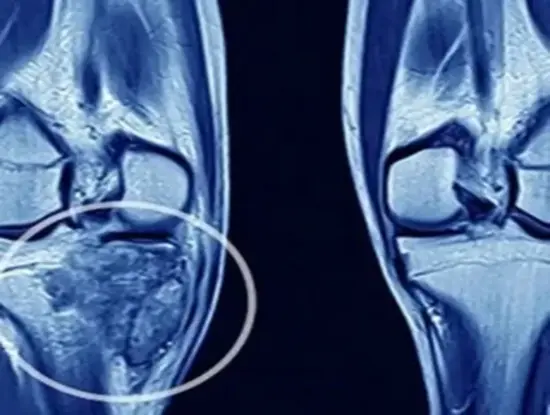

The danger of this particular symptom is that, initially, younger individuals might find it as just another of their common growing pains, while older ones would dismiss it as merely arthritis. However, if it continues unabated for more than two weeks without other obvious causes, it is time to seek a physician’s opinion. Orthopedic oncologists emphasize the need for early X-rays or MRI to investigate any possible bone pain. The diagnosis can quickly confirm whether the pain is from cancer or not so that you can start timely intervention if necessary, with all the advanced capabilities available at bone cancer treatment centers.

Severe, non-traumatic fractures are truly alarming sights for the diagnosis of bone cancers. As a result of these cancerous lesions weakening the bone architecture, any patient may break a bone in the context of relatively harmless daily activities. A pathologic fracture is, therefore, almost always a sign of an advanced underlying bone cancer, particularly in cases where other signs and symptoms may have been mild or even missed altogether.

Pathologic fractures from bone cancer tend to heal poorly without proper treatment of the underlying condition. Orthopedic surgeons deal with bone cancer patients daily with atypical fractures as the first meaningful complaint. This often leads to a diagnosis of cancer. Current treatment practices found in cancer care centers can repair the fracture itself through surgical stabilization. Thus, providing comprehensive care for the cancerous lesion, including limb-sparing measures that allow for the preservation of function along with tumor removal.